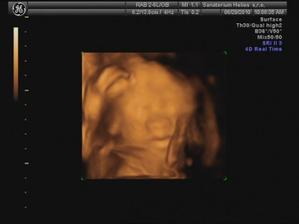

29.6. jdeme na 3D ultrazvuk 🙂 těšíme se... - bylo to úžasný 🙂 cena sice vyšší, ale jedna barevná fotka tištěná, 3 fotky na mail a téměř půlhodinové video, ze kterého jsme si doma udělali ještě asi 120 fotek 🙂